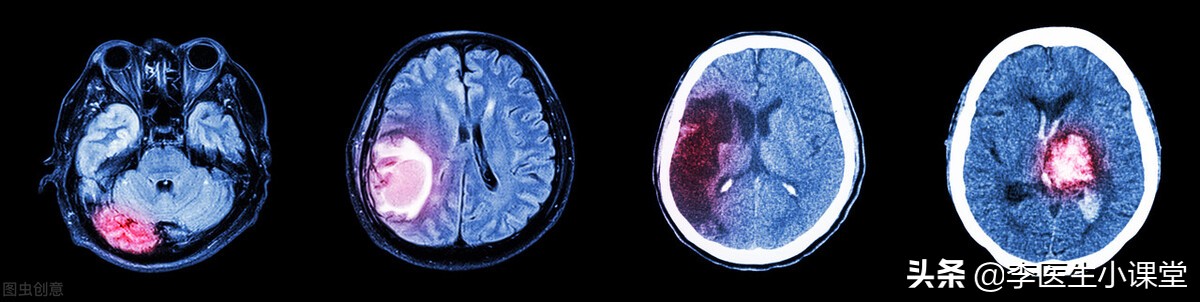

脑溢血也就是我们通常所说的脑出血(ICH), 是一种非外伤引起的脑实质内出血,血液从血管中溢出到脑组织中, 出血部位常出现在大脑半球、脑干以及小脑等处,在急性心脑血管疾病中脑出血患者占比较多,且致死率较高。

临床上根据大脑内血肿的发展过程,将其分为急性期、吸收期以及囊变期。